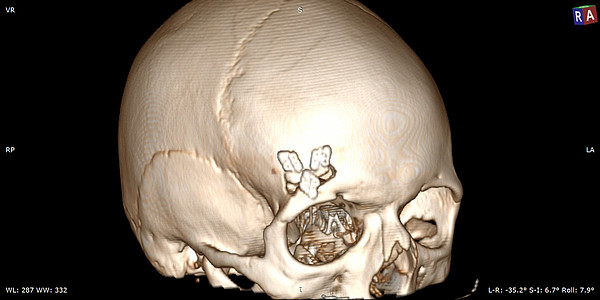

Недавно специалисты КОКБ применили технологию keyhole при оперативном лечениии жительницы Кировской области. У нее нашли объемное образование основания черепа. Опухоль извлекли через разрез вдоль брови, длиной всего в 3 сантиметра. Подход к опухоли осуществлялся по основанию черепа, то есть в пространстве между мозгом и костными структурами.

– Для расчета оптимальной траектории использовалась нейронавигация, позволившая точно определить локализацию опухоли и свести к минимуму повреждение окружающего мозгового вещества. У пациентки сохранены все двигательные, чувствительные, мнестические функции, кроме того достигнут и хороший косметический результат, – сообщил заведующий отделением.